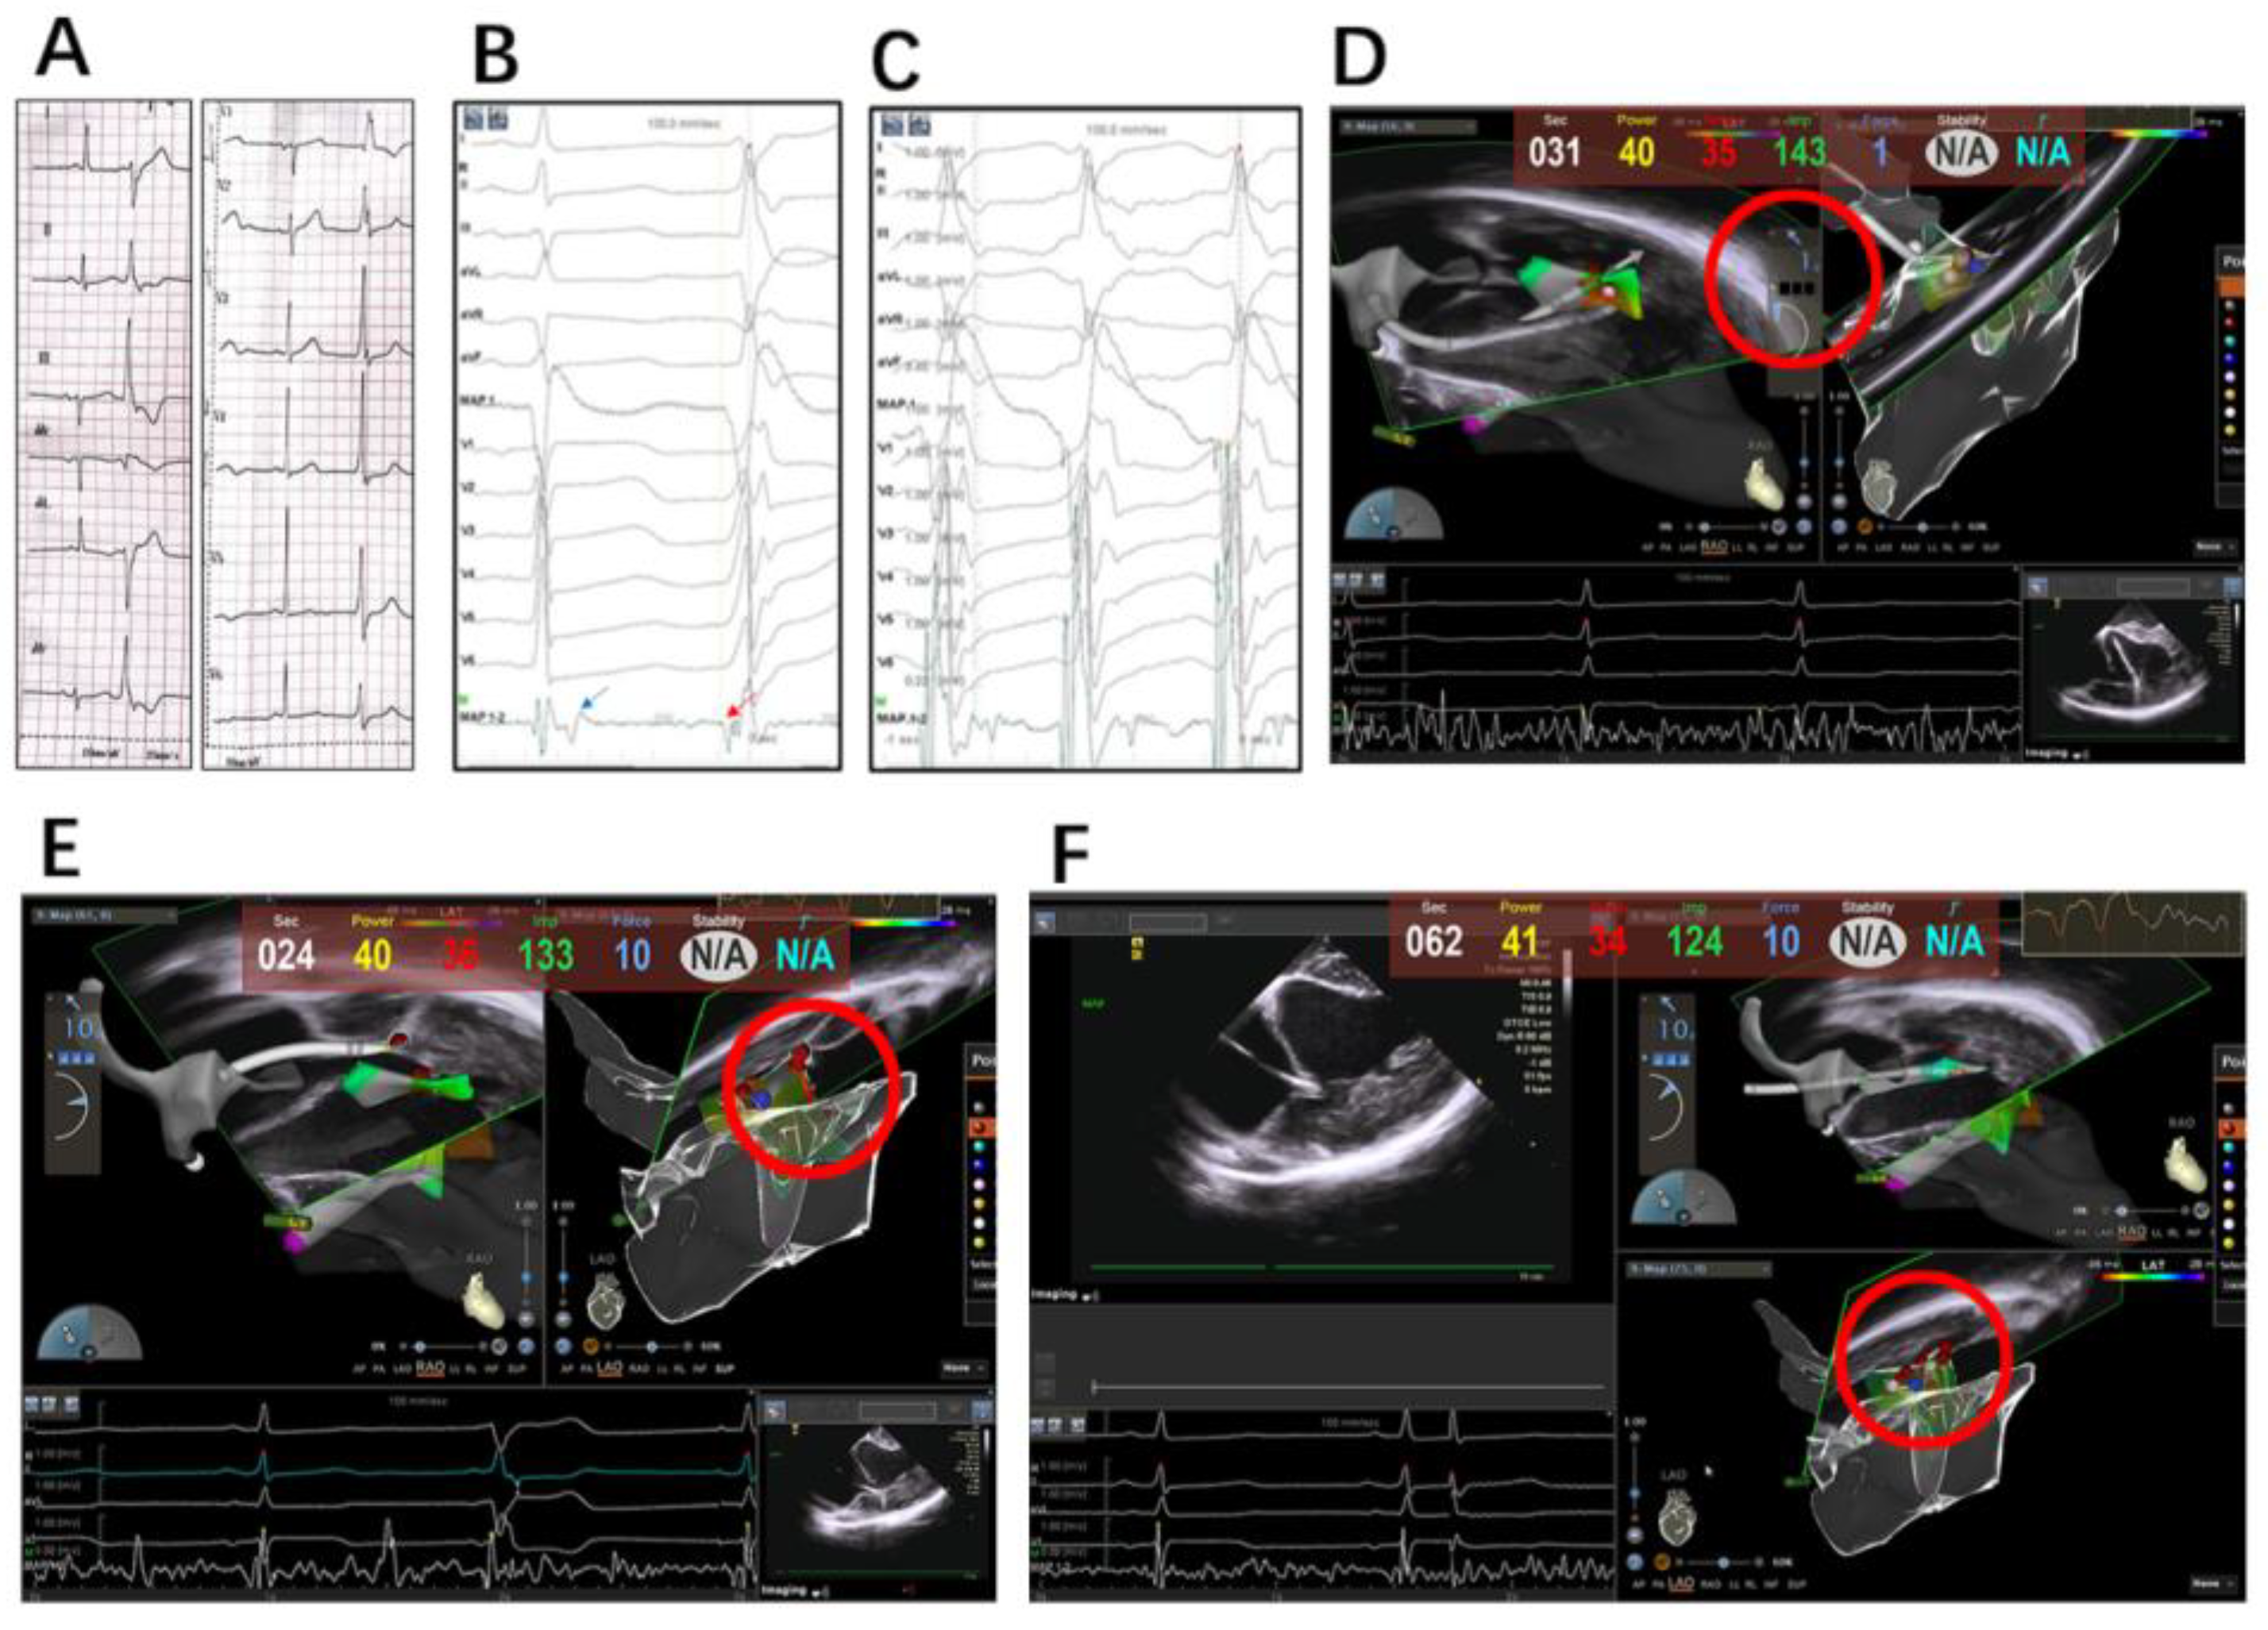

2.2. Electrophysiology Study, Mapping and Ablation

2.2.1. Intracardiac Echocardiography

2.2.2. Mapping and Ablation

4.1. Integration of Echocardiography and 3D Mapping

4.2. Contact Force

4.3. Optimizing Ablation Lesions